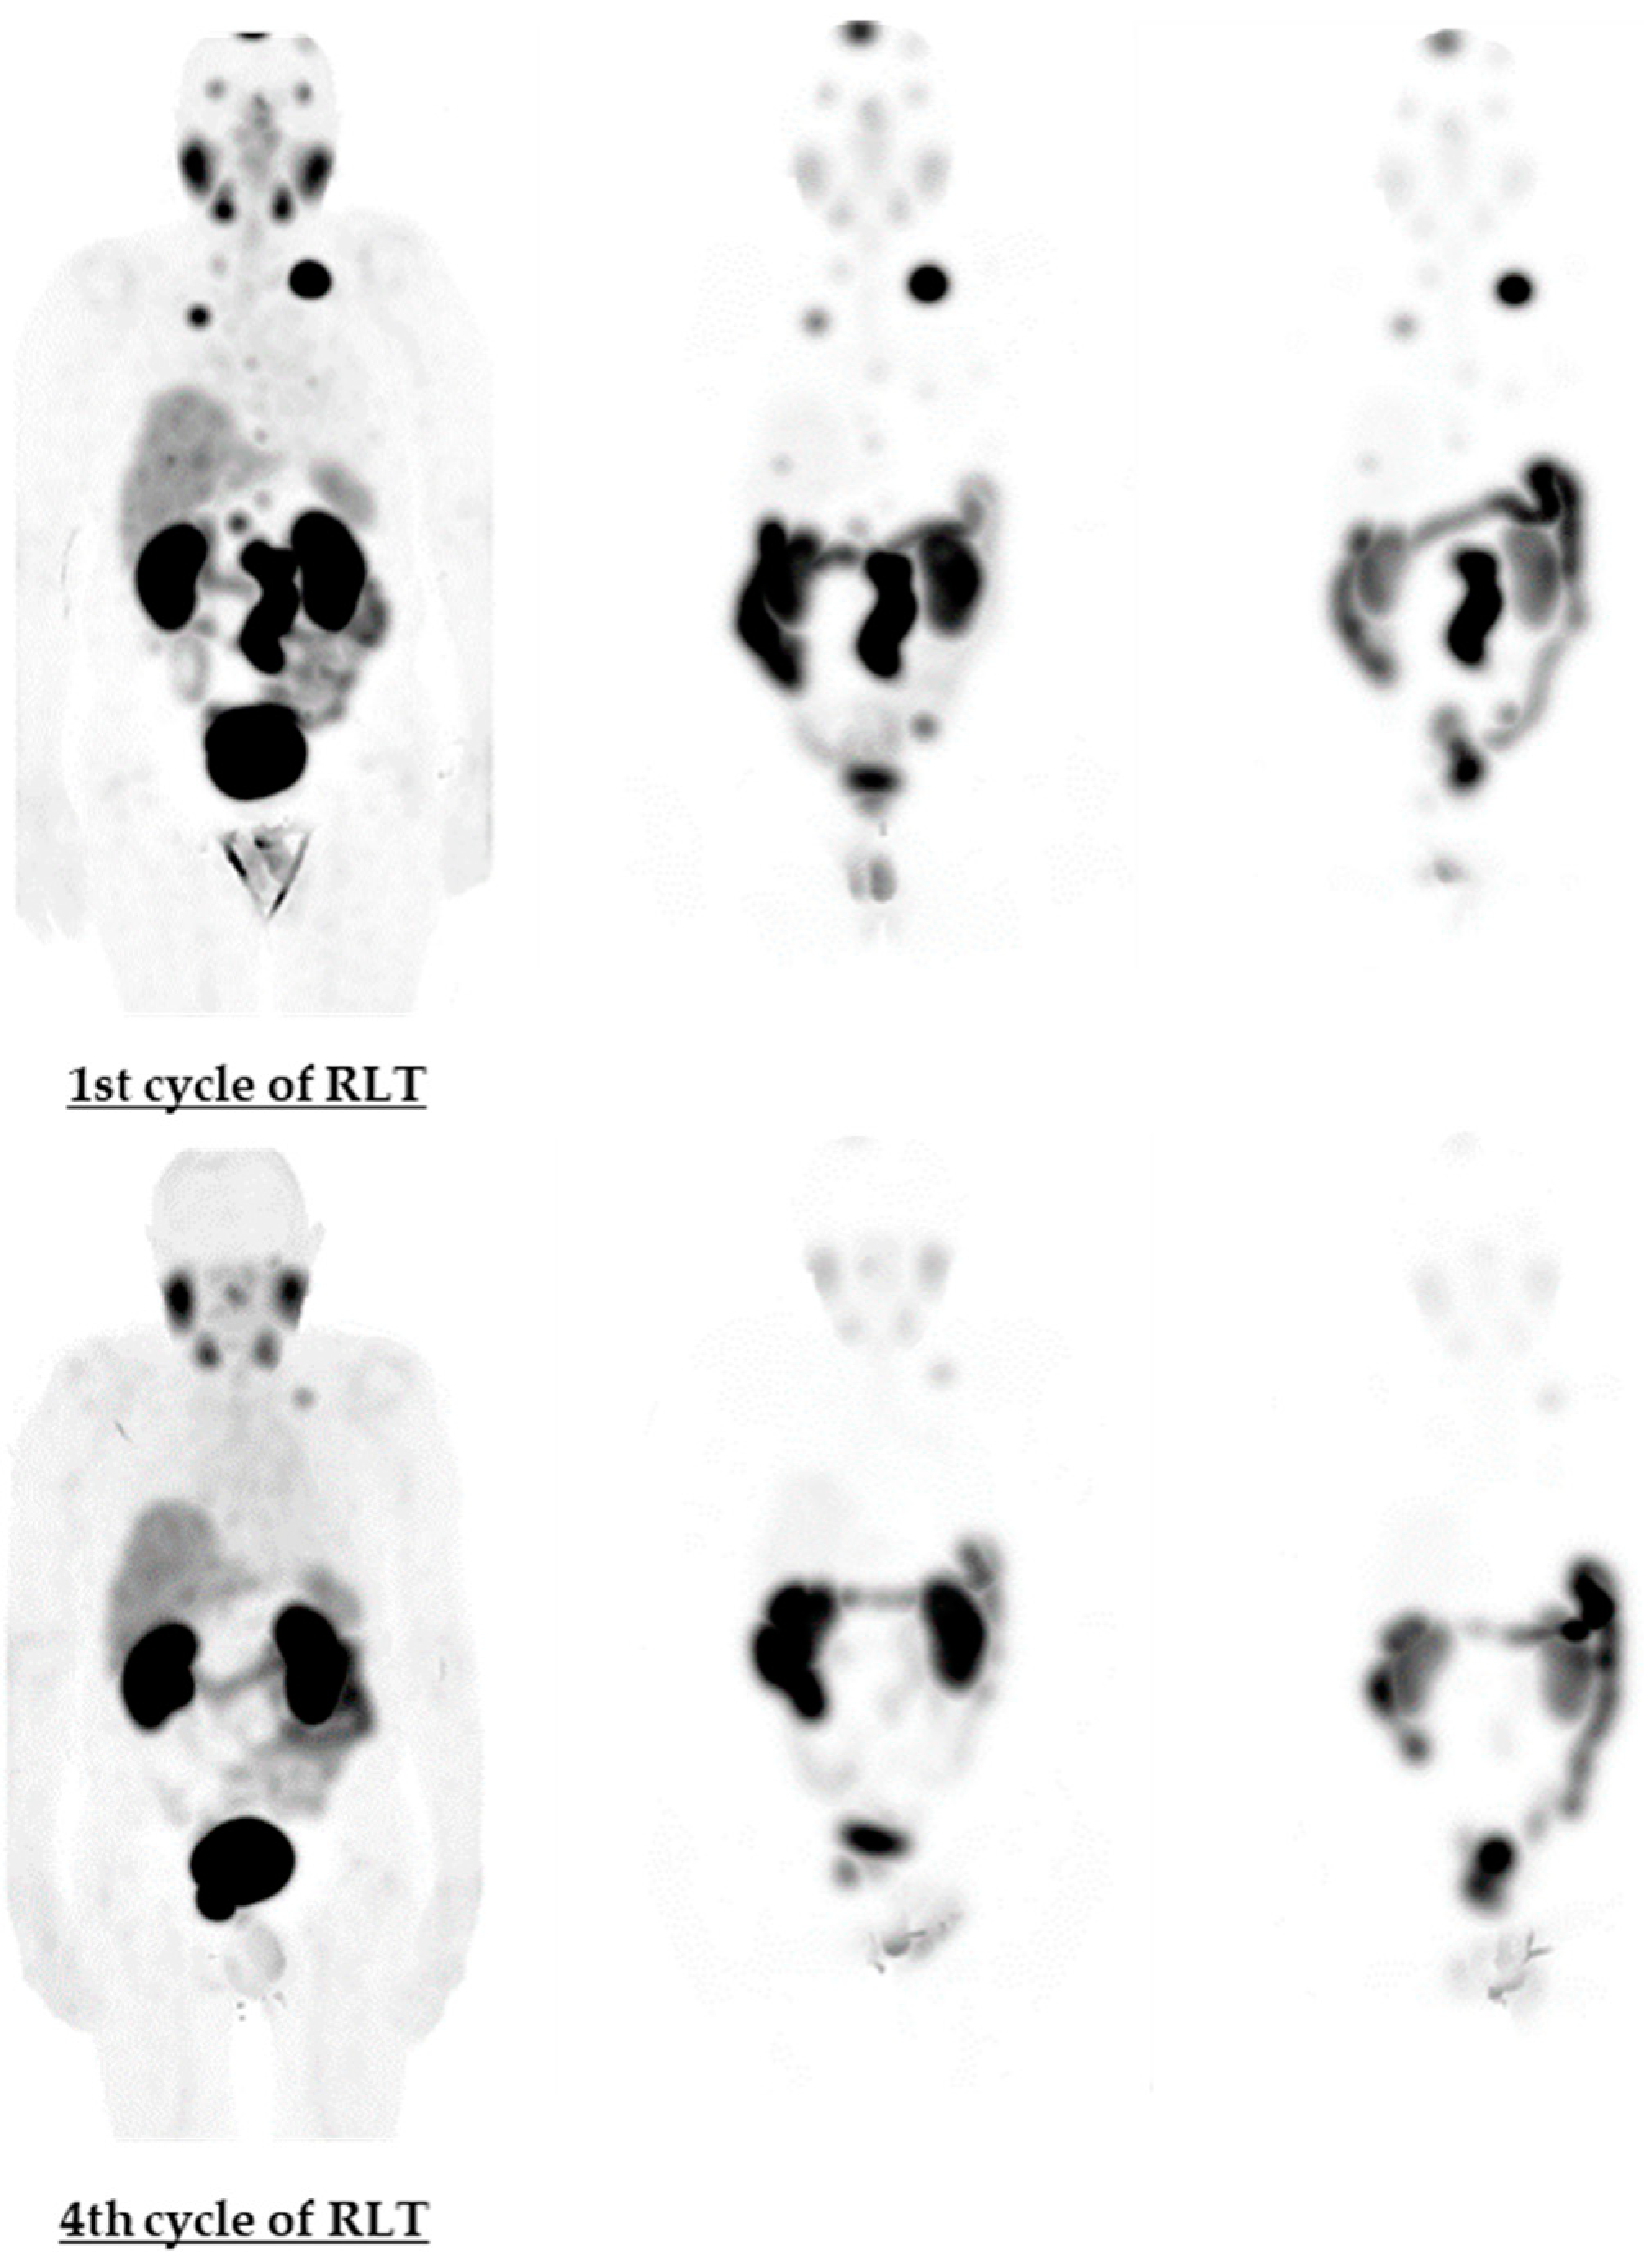

| Cycle of RLT | LLN | DLN1 | DLN2 | B1 | B2 | B3 |

|---|---|---|---|---|---|---|

| Gy/GBq | ||||||

| 1st | 6.89 | 25.57 | 6.8 | 5.55 | 6.25 | 3.75 |

| 2nd | 6.03 | 9.43 | 3.04 | 0.64 | 1.85 | 1.96 |

| 3rd | 2.84 | 8.3 | 2.59 | 0.48 | 0.97 | 1.86 |

| 4th | 2.72 | 7.24 | 2.91 | N/A | N/A | N/A |

| Cycle of RLT | LLN | DLN1 | DLN2 | B1 | B2 | B3 | |

|---|---|---|---|---|---|---|---|

| 1st; Volume (mL) | 0.67 | 3.9 | 0.6 | 1.5 | 0.4 | 0.3 | |

| SUVmax at | 4 h | 2.69 | 33.56 | 24.73 | 9.5 | 5.72 | 2.9 |

| 24 h | 2.64 | 14.36 | 11.2 | 4.21 | 2.33 | 0.96 | |

| 48 h | 2.06 | 9.8 | 8.9 | 2.61 | 1.56 | 0.66 | |

| 2nd; Volume (mL) | 0.37 | 1.22 | 0.4 | 1.5 | 0.4 | 0.3 | |

| SUVmax at | 4 h | 1.14 | 5.73 | 3.56 | 1.83 | 1.23 | 1.32 |

| 24 h | 0.73 | 2.28 | 1.56 | 0.92 | 0.42 | 0.27 | |

| 48 h | 0.68 | 1.43 | 1.28 | 0.64 | 0.29 | 0.15 | |

| 3rd; Volume (mL) | 0.1 | 0.82 | 0.26 | 1.5 | 0.4 | 0.3 | |

| SUVmax at | 4 h | N/A | 3.12 | N/A | 1.02 | N/A | N/A |

| 24 h | N/A | 1.19 | 0.94 | 0.52 | N/A | N/A | |

| 48 h | N/A | 0.76 | N/A | 0.35 | N/A | N/A | |

| 4th; Volume (mL) | 0.1 | 0.5 | 0.13 | 1.5 | 0.4 | 0.3 | |

| SUVmax at | 4 h | N/A | 1.96 | N/A | 0.66 | N/A | N/A |

| 24 h | N/A | 0.79 | 0.5 | 0.32 | N/A | N/A | |

| 48 h | N/A | 0.52 | N/A | 0.22 | N/A | N/A | |